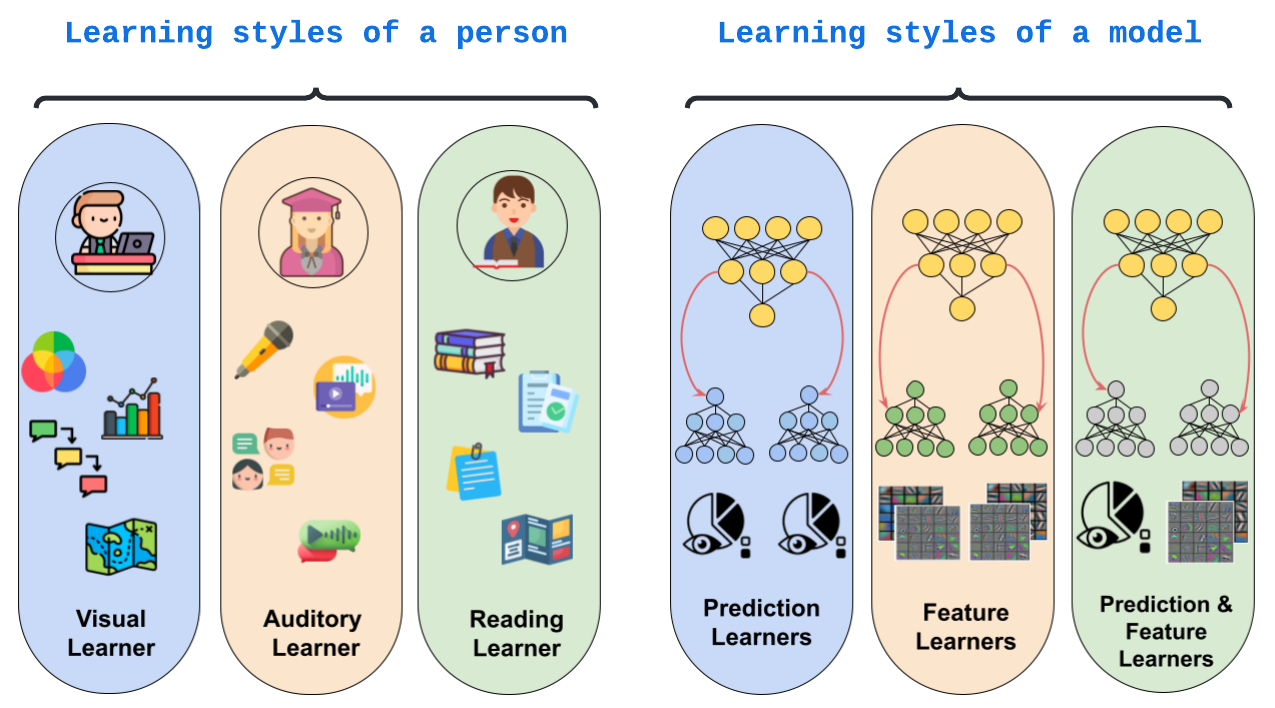

Learning style refers to a type of training mechanism adopted by an individual to gain new knowledge. As suggested by the VARK model, humans have different learning preferences, like Visual (V), Auditory (A), Read/Write (R), and Kinesthetic (K), for acquiring and effectively processing information. Our work endeavors to leverage this concept of knowledge diversification to improve the performance of model compression techniques like Knowledge Distillation (KD) and Mutual Learning (ML). Consequently, we use a single-teacher and two-student network in a unified framework that not only allows for the transfer of knowledge from teacher to students (KD) but also encourages collaborative learning between students (ML). Unlike the conventional approach, where the teacher shares the same knowledge in the form of predictions or feature representations with the student network, our proposed approach employs a more diversified strategy by training one student with predictions and the other with feature maps from the teacher. We further extend this knowledge diversification by facilitating the exchange of predictions and feature maps between the two student networks, enriching their learning experiences. We have conducted comprehensive experiments with three benchmark datasets for both classification and segmentation tasks using two different network architecture combinations. These experimental results demonstrate that knowledge diversification in a combined KD and ML framework outperforms conventional KD or ML techniques (with similar network configuration) that only use predictions with an average improvement of . Furthermore, consistent improvement in performance across different tasks, with various network architectures, and over state-of-the-art techniques establishes the robustness and generalizability of the proposed model.

In this work, we extend the knowledge distillation paradigm with the concept of diverse learning styles from classroom dynamics. A learning style refers to a type of training mechanism that an individual prefers to use to gain new knowledge. For example, as depicted in Figure 1, the VARK model assumes four types of learners – Visual, Auditory, Reading & Writing, and kinesthetic. Taking inspiration from this idea, we propose an enriched knowledge transfer protocol that incorporates the idea of different learning styles in terms of knowledge diversification. Consequently, we combine KD with ML in a single-teacher, multi-student framework to enable collaborative learning where the teacher imparts knowledge to the students, and the students also learn from each other. Unlike conventional KD techniques, where the teacher shares the same knowledge with all the students, we propose to train individual student networks with varying forms of information from the teacher. Similarly, students exchange different types of information in the form of final predictions and intermediate layer features.

Figures 2 (a) and (b) depict the standard distillation techniques used for knowledge distillation and mutual learning. Extension of KD to a single teacher and multiple student networks is also quite standard. Recently, [38] proposed a combination of KD and ML, where in addition to sharing information by the teacher, students also exchange information, as shown in Figure 2 (c). In such configurations, the ensemble of student networks is used for the final prediction. In the current work, we investigate the benefit of knowledge diversification in four different distillation techniques- (i) Offline KD-only framework as shown in Figure 2 (a) (ii) Online KD-only framework (iii) ML-only framework with two students as shown in Figure 2 (b), and (iv) combined KD + ML frameworks with one teacher and two students as shown in Figure 2 (c).

Leveraging the idea that different learning styles can improve the understanding of learners, we propose to train individual student networks with different information from the teacher. The teacher shares final predictions with one student and intermediate layer features with another. Similarly, in the ML framework, students engage in information exchange, sharing predictions and intermediate-layer features with one another. To underscore the significance of knowledge diversification, we train each of the above-mentioned distillation techniques with three different information-sharing strategies (V1, V2, and V3), as shown in Table 1(c). Furthermore, we use student networks with identical architectures to emphasize the influence of different learning styles.